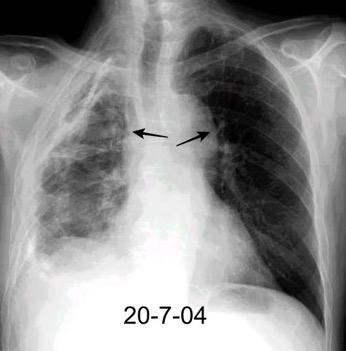

By-pass coronario 21-10-03

Síndrome de afectación postcardiaca (postcardiac injury)

Post infarto 1-7 % (Dressler)

Trauma cerrado Implantación marcapasos

Cirugía cardiaca. 17-31% (Post.pericardiotomía)

3707 pacientes 29 Derrames (0,78%) > de 25% del hemitórax

Todas menos 2 Izdos.

Angioplastia